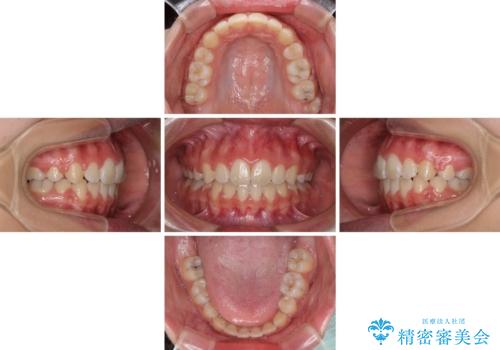

前歯部の突出と開咬は、舌突出癖によるものでしたので、舌のトレーニングをしっかりと行っていただき、1年半程度と短期間で治療を終えることができました。

口元を積極的に引っ込めるために、上下左右の第一小臼歯を4本抜歯することとしました。